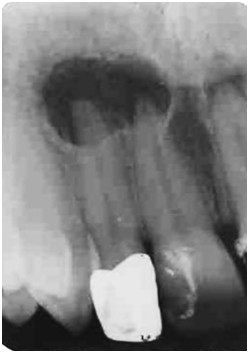

Pacjentka lat 45 zgłosiła się z nawracającym bólem i obrzękiem okolicy przednich siekaczy 11 i 12. W badaniu klinicznym - zęby bolesne na opuk pionowy, przedsionek jamy ustnej w okolicy 11 i 12 lekko bolesny. Ząb 12 okoronowany, w 11 duże wypełnienie. Obrzęk od strony podniebienia w projekcji wierzchołków korzeni zębów 11 i 12. Stan przyzębia prawidłowy. Brak patologicznej ruchomości zębów. Brak objawów ogólnych. Obraz Rtg przedstawiono poniżej. Jaka jest diagnoza i postępowanie terapeutyczne?